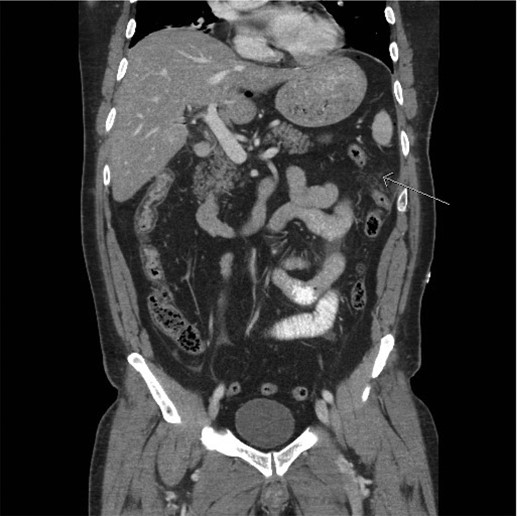

A CT scan demonstrated significant soft tissue stranding/edema of the omentum in the left hemi-abdomen. In addition, there was mild ascites and multiple scattered locules of air (Figs 3–5). No other abnormality of the small or large bowel was identified. He was admitted for observation and broad-spectrum antibiotic therapy was initiated. On post admission day 2, he became diffusely peritonitic, febrile with a temperature of 39.1°C and his oxygen requirements increased to 12 l/min.

CT scan (frontal view) demonstrating multiple locules of air (arrows).

CT scan (frontal view) demonstrating stranding/edema to the omentum (arrow).

Our case demonstrates the diagnostic dilemma that accompanies delayed bowel injuries. Laboratory tests often give nonspecific results that seldom point to a diagnosis [1]. Imaging studies also fail to establish the etiology. Our CT scan failed to demonstrate significant intraperitoneal free air (Figs 3–5). In addition, oral contrast was utilized, but gross extravasation was not identified.